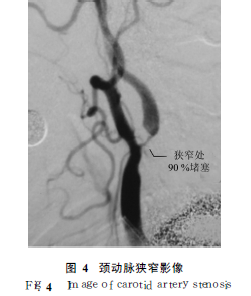

脑中风的另一个特点是,如果中风的病因如高血压、颈动脉狭窄等不被去除的话,中风会反复发作。我国临床资料的分析表明,40%的门诊中风病例属第2次以上发作。近数十年来,美国针对引致缺血性脑中风的重要因素一颈动脉斑块形成造成的狭窄开展了大量的筛查与干预工作,从而使脑中风的发病率和死亡率大幅度下降。而我国在以往的心脑血管病的防控中,对高血压的筛查和控制比较重视,但对颈动脉狭窄问题注意不够,甚至在常规的干部体检中也没有颈动脉筛查项目(见图3和图4)因此,大量脑中风前期的患应对脑中风的服务架构上也不能有效满足不同病情发展阶段患者的服务需求。目前,医疗服务的提供是按专业技术科别划分的,如神经内科、神经外科等,且科室之间的联系不甚紧密,而患者病情的发展却是渐进的,需要提供连续的、综合性的干预措施。需求和服务提供架构二者之间的矛盾制约了服务质量的提高。其二,以往的临床服务,多为坐等病人模式。对脑中风这种疾病来讲,等到病人找医生时,绝大多数患者已失去了最佳的治疗时机。

针对以上问题,近几年中美脑中风协作组开展了服务模式改革探索,取得了一定进展。首先,按照“以病人为中心”的服务提供原则,组建技术团队与单元。由心血管内科、神经内科、介入治疗和神经血管外科医生组成的联合团队,为每一例患者提供综合性服务。这种服务的好处是,各种不同服务技术之间可以实现无缝衔接,尽量为病人争取救治时间,减轻疾病损害,防止或减少并发症的产生。其次是走出医院,深入基层,开展高危人群筛查并实施个体化的干预。脑中风高危患者既有共同的特征,又有各自的重点问题。因此,通过群体筛查,明确每位患者需干预的关键点,落实ABCDE方控策略(A抗栓治疗;B控制血压和体重;Q降低胆固醇、戒烟、开展支架及颈动脉内膜剥脱术;D控制糖尿病、进行膳食调整;E开展健康教育、体育锻炼、定期查体)在中美脑中风协作组的试点工作中,许多由于颈动脉狭窄造成的脑中风的体征,如一侧肢体活动障碍或丧失肌力、失语、由于缺血性眼病造成的视力明显下降或失明等,在及时解除颈动脉狭窄后,均得到了明显改善或恢复。所以,对高危人群颈动脉状况的筛查,既可对狭窄不甚严重的患者及早给以行为指导或药物干预,延缓其狭窄进展,又可对狭窄严重的患者釆取手术或介入治疗,去除其发生脑中风的病源,减少脑中风的发生及其后的伤残。这种临床工作理念和方式的调整,临床和公卫的战略融合,已在慢性疾病的防控工作中显示出了明显的社会效益和经济效益,值得进一步的探索和推广。